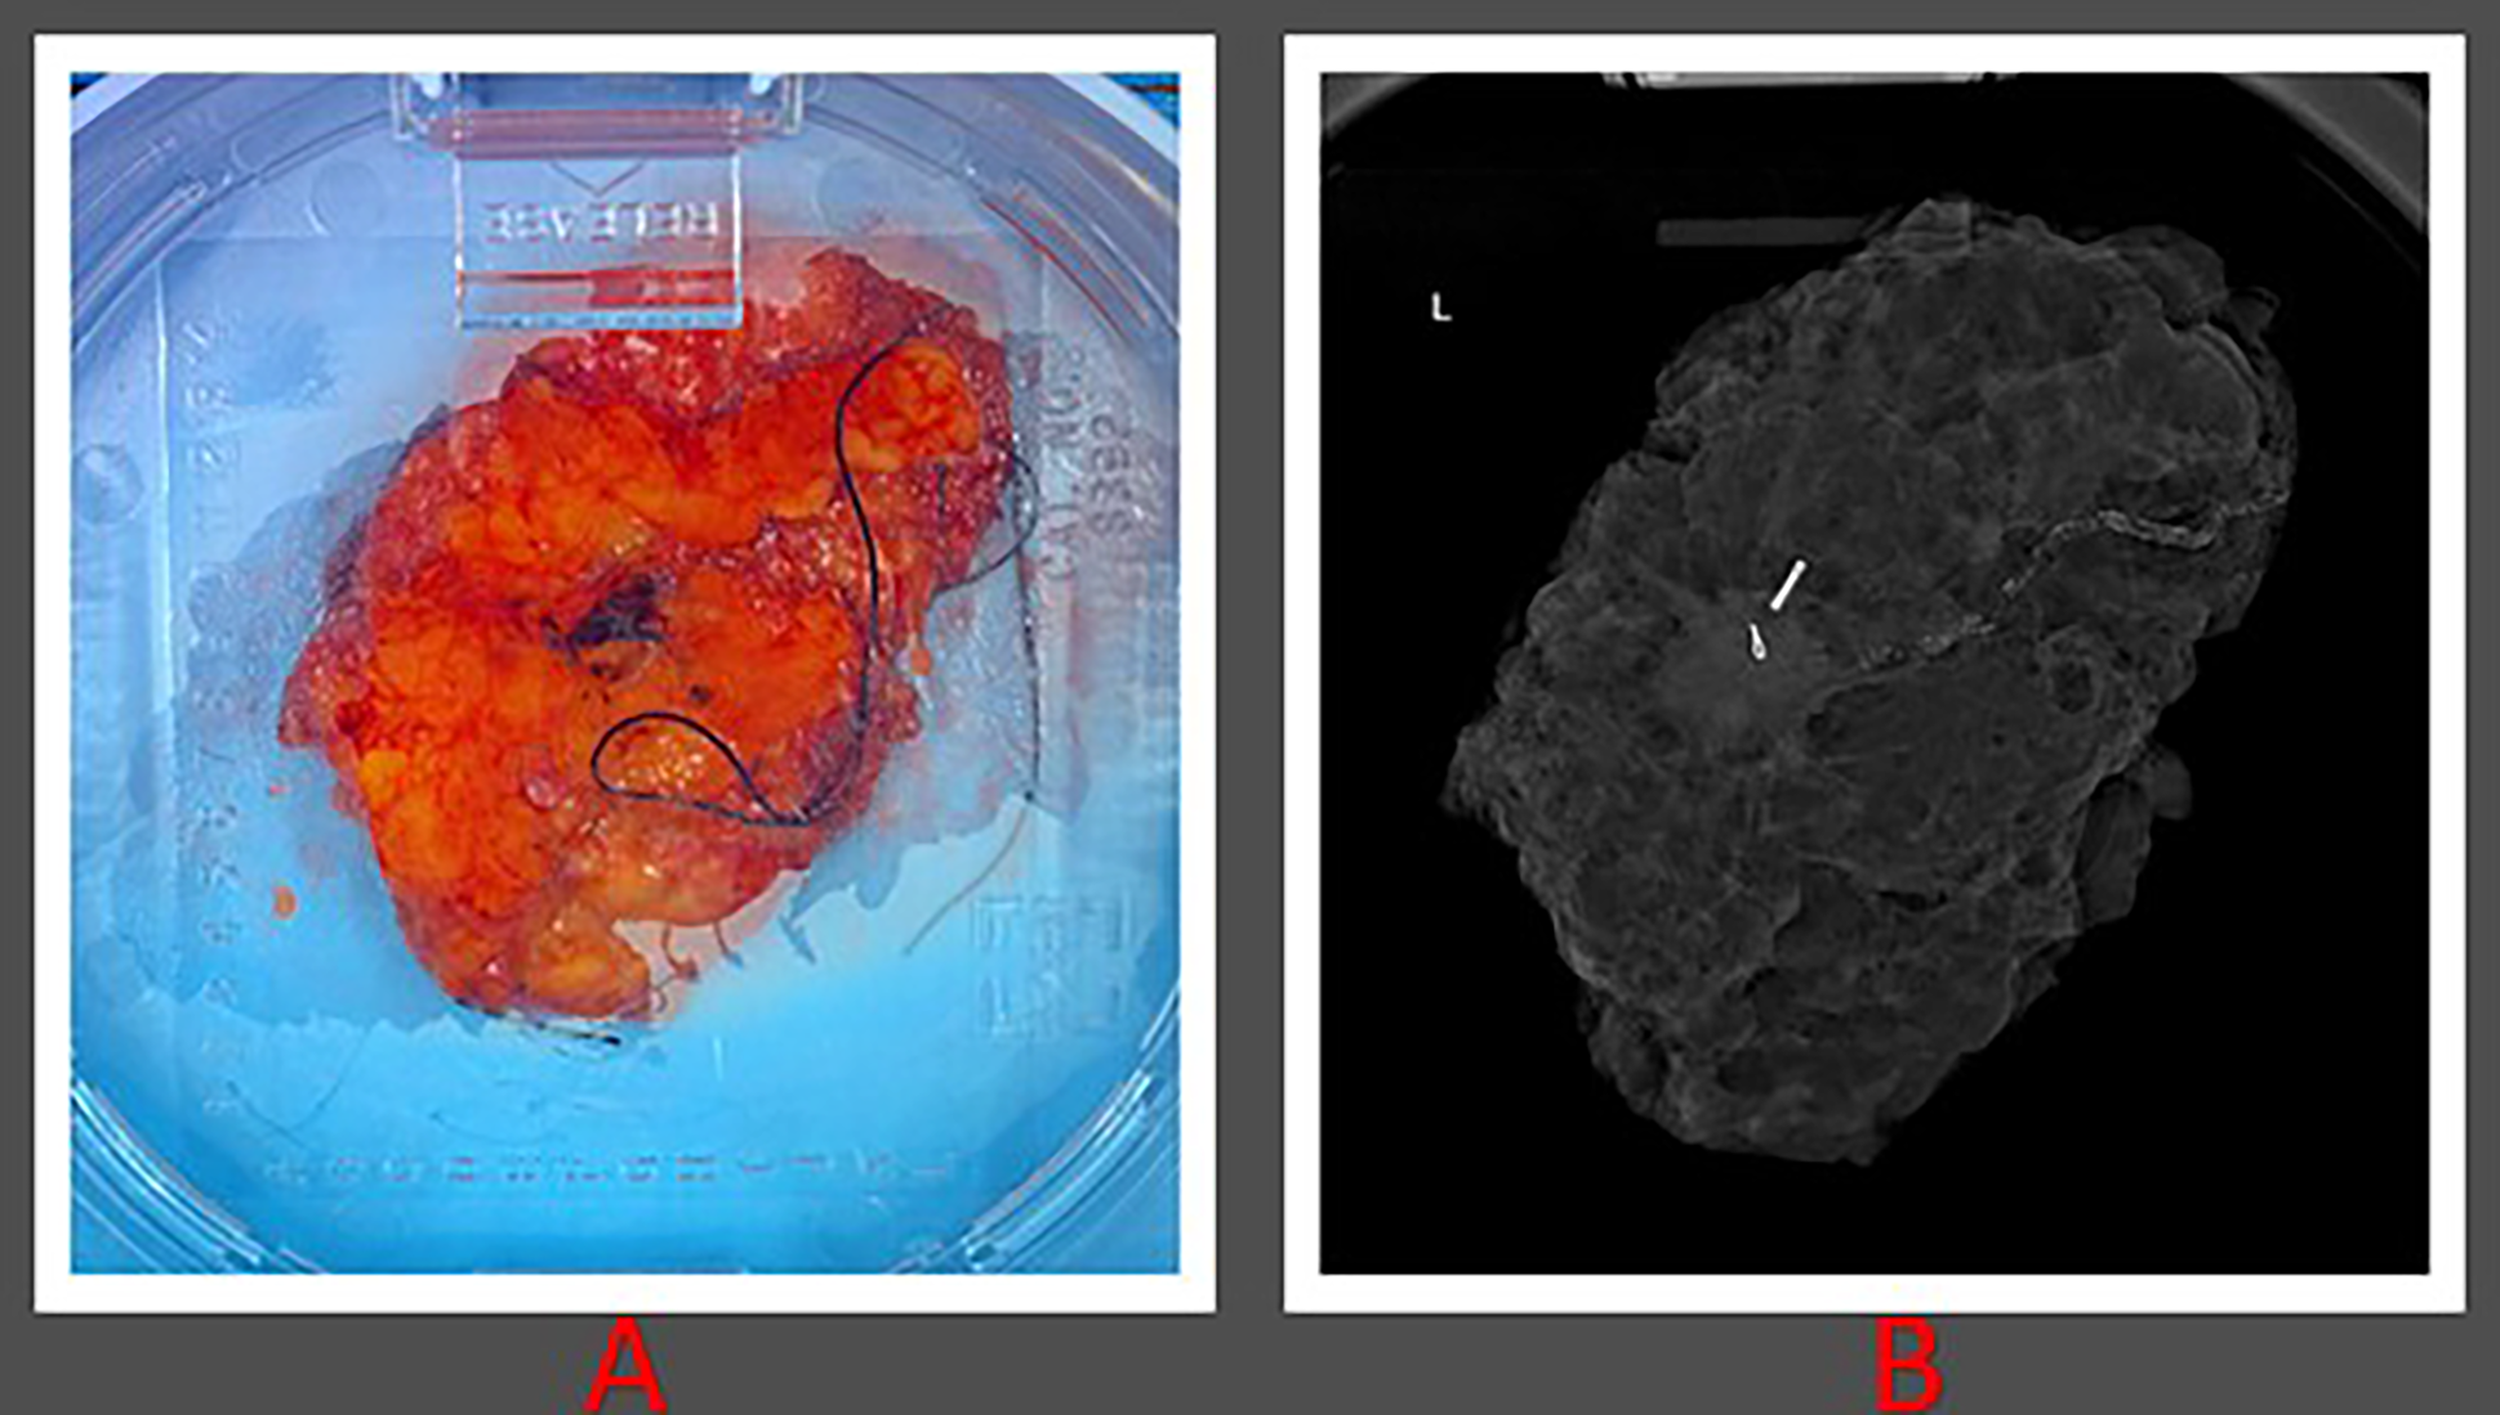

Figure 2 Histopathological images of patient 1. (A) Gross lumpectomy specimen measuring 10 cm in dimension extending from superior to inferior margin and measuring 6.2 cm extending from lateral to medial margin. (B) Lumpectomy specimen with presence of radiological seed.

Wide local excision was performed and TARGIT-IORT was delivered during surgery using the Intrabeam 600 (Zeiss, Oberkochen, Germany) (Figure 2). Ultrasound was then used to measure the distance from the applicator to the skin with the closest bridge being inferior at 10.6 mm. IORT was delivered with a 40-mm diameter spherical applicator, delivering 20 Gy to the surface of the surgical margin in direct contact with the applicator for a duration of 25 minutes. In vivo dosimetry was performed by placing an optically stimulated luminescence dosimeter (OSLD) under the radiation shield on the skin surface in close proximity to the pacemaker site during treatment. The measured absorbed dose resulting from the Zeiss INTRABEAM IORT system radiation on the skin surface in close proximity to the pacemaker site was measured to be 0.23 Gy, using the same methodology described previously by our group (16).

The surgery and TARGIT procedure were both successful. The patient tolerated the procedure very well, and there was no malfunction of the pacemaker device throughout the surgery or IORT. The patient made an uneventful recovery and was sent home the same day. Histology confirmed the presence of an 18 mm grade 2 invasive ductal carcinoma with admixed lobular features that had been fully removed with clear margins. The tumor tested positive for ER/PR but negative for Her-2. As part of her adjuvant endocrine therapy, a treatment plan with aromatase inhibitor was decided.